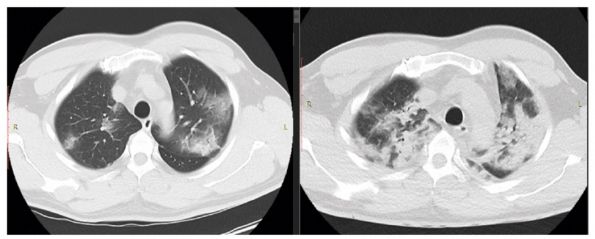

Кт динамика

Кт динамика 110 фото